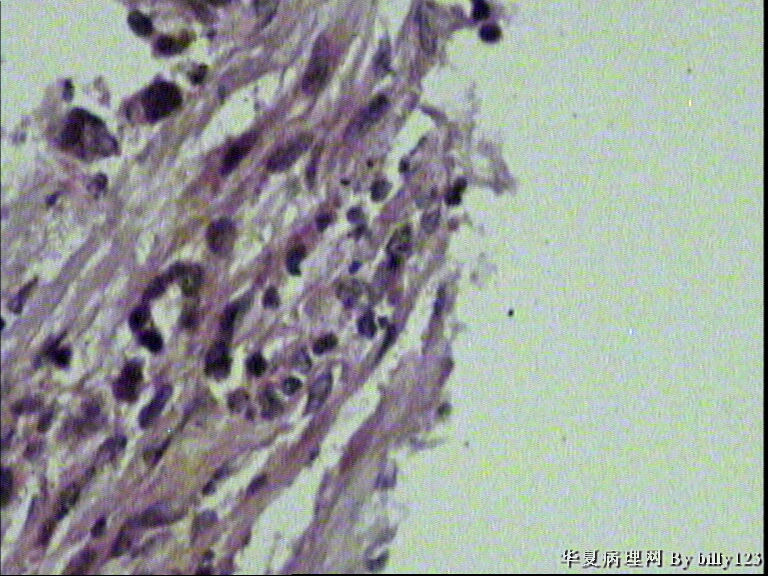

纤支镜活检,女性,75岁,请各位老师指教!

图2